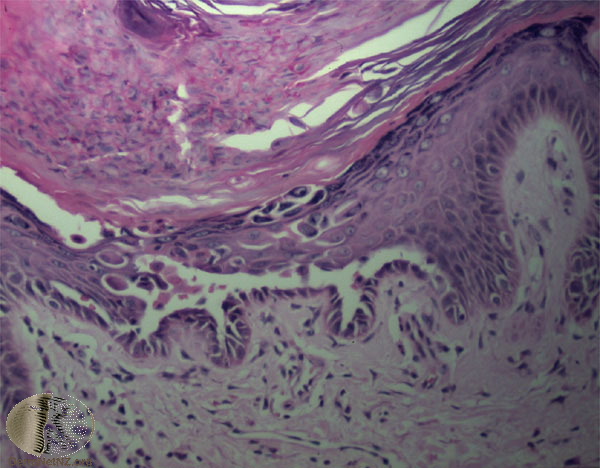

The characteristic changes in Darier’s disease include the following: (a) a peculiar form of dyskeratosis resulting in the formation of corps ronds and grains; (b) suprabasal acantholysis leading to the formation of suprabasal clefts or lacunae; and (c) irregular upward proliferation into the lacunae of papillae lined with a single layer of basal cells, so-called villi (Fig. 6-27). There are also papillomatosis, acanthosis, and hyperkeratosis. The dermis shows a chronic inflammatory infiltrate. In some cases, there is downward proliferation of epidermal cells into the dermis.

The corps ronds occur in the upper stratum malpighii, particularly in the granular and horny layers; grains are found in the horny layer and as acantholytic cells within the lacunae. Corps ronds possess a central homogeneous, basophilic,

pyknotic nucleus that is surrounded by a clear halo. By virtue of size and the conspicuous halo, corps ronds stand out clearly . Peripheral to the halo lies basophilic dyskeratotic material as a shell . The nonstaining halo in some instances is partially replaced by homogeneous, eosinophilic dyskeratotic material . Compared with the corps ronds, the grains are much less conspicuous. They resemble parakeratotic cells but are somewhat larger. The nuclei of grains are elongated and often grain shaped and are surrounded by homogeneous dyskeratotic material that usually stains basophilic but may stain eosinophilic. The lacunae represent small, slitlike intraepidermal vesicles most commonly located directly above the basal layer. They contain acantholytic cells and show premature partial keratinization. Because of shrinkage, some of them are elongated, and these then appear identical with the grains in the horny layer. The villi projecting into the lacunae may be quite tortuous, so on histologic examination, some of them appear in cross section as rounded dermal structures lined by a solitary row of basal cells .